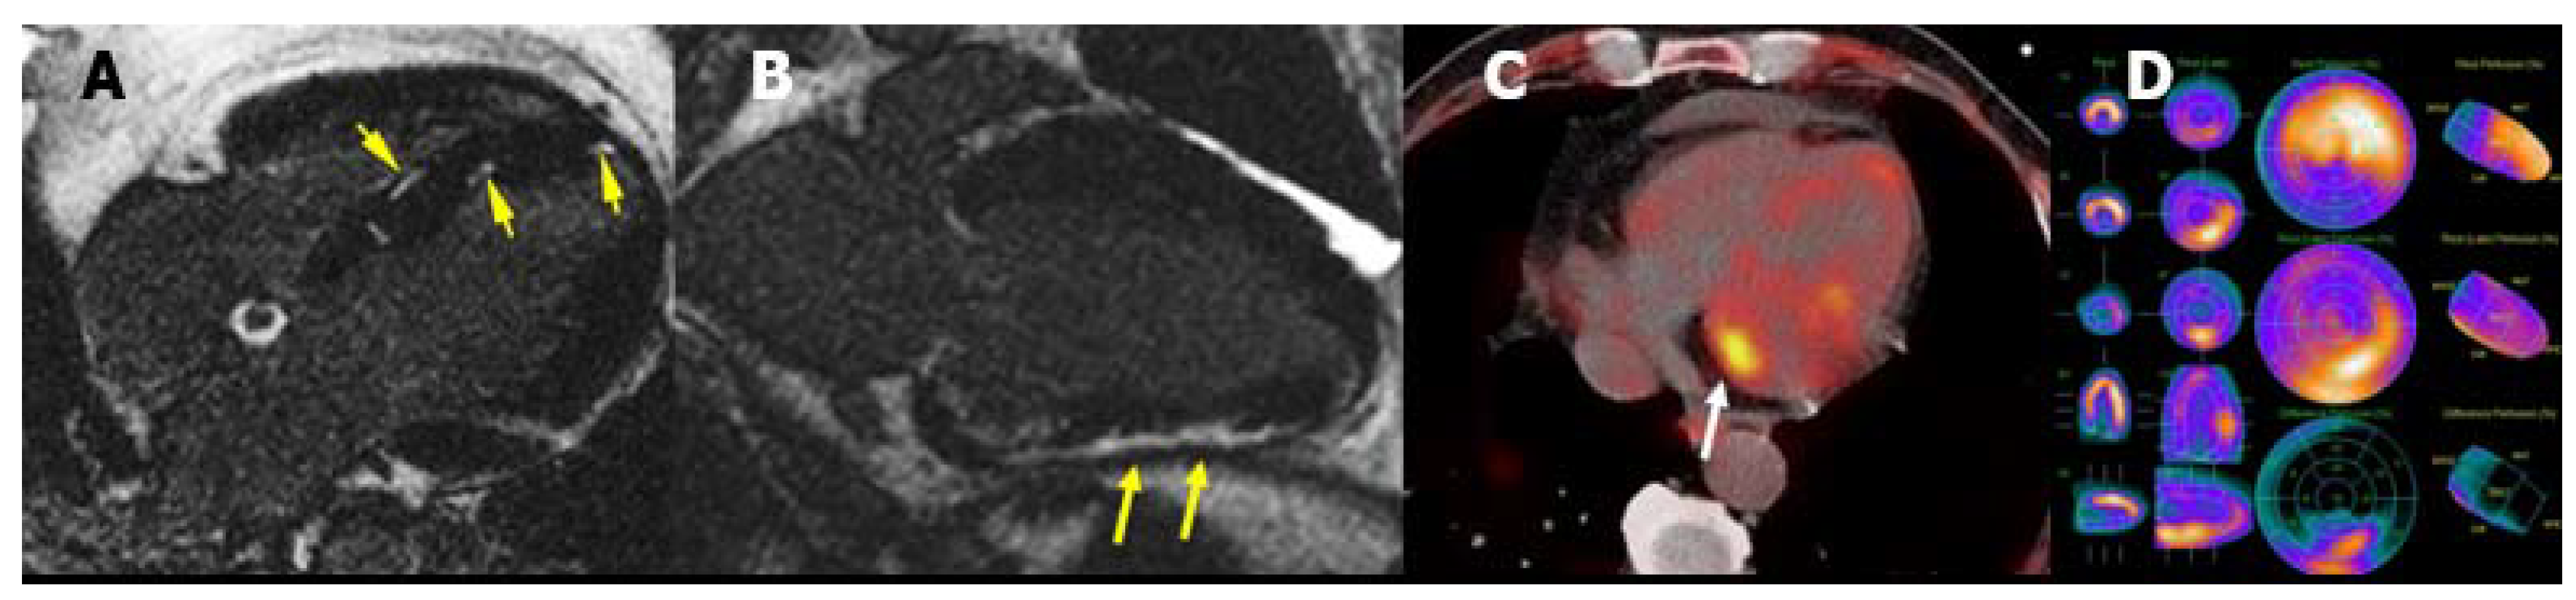

4.3. Fabry Disease

- Nappi, C.; Altiero, M.; Imbriaco, M.; Nicolai, E.; Giudice, C.A.; Aiello, M.; Diomiaiuti, C.T.; Pisani, A.; Spinelli, L.; Cuocolo, A. First experience of simultaneous PET/MRI for the early detection of cardiac involvement in patients with Anderson-Fabry disease. Eur. J. Nucl. Med. Mol. Imaging 2015, 42, 1025–1031. [Google Scholar] [CrossRef]

- Imbriaco, M.; Pellegrino, T.; Piscopo, V.; Petretta, M.; Ponsiglione, A.; Nappi, C.; Puglia, M.; Dell’Aversana, S.; Riccio, E.; Spinelli, L.; et al. Cardiac sympathetic neuronal damage precedes myocardial fibrosis in patients with Anderson-Fabry disease. Eur. J. Nucl. Med. Mol. Imaging 2017, 44, 2266–2273. [Google Scholar] [CrossRef] [Green Version]